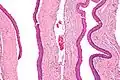

| Micrograph of an odontogenic keratocyst. H&E stain. | |

Odontogenic keratocysts have a diagnostic histological appearance. Under the microscope, OKCs vaguely resemble keratinized squamous epithelium;[15] however, they lack rete ridges and often have an artifactual separation from their basement membrane.[2]

The fibrous wall of the cyst is usually thin and uninflamed. The epithelial lining is thin with even thickness and parakeratinised with columnar cells in the basal layer which have focal reverse polarisation (nuclei are on the opposite pole of the cell).[13] The basal cells are an indication of the odontogenic origin as they resemble pre-ameloblasts. The epithelium can separate from the wall, resulting in islands of epithelium. These can go on to form 'satellite' or 'daughter' cysts, leading to an overall multilocular cyst.[10] Presence of daughter cysts is particularly seen in those with NBCCS.[13] Inflamed cysts show hyperplastic epithelium which is no longer characteristic of OKCs and can have resemblance to radicular cysts instead. Due to areas of focal inflammation, a larger biopsy is required for correct diagnosis of odontogenic keratocysts.[10]